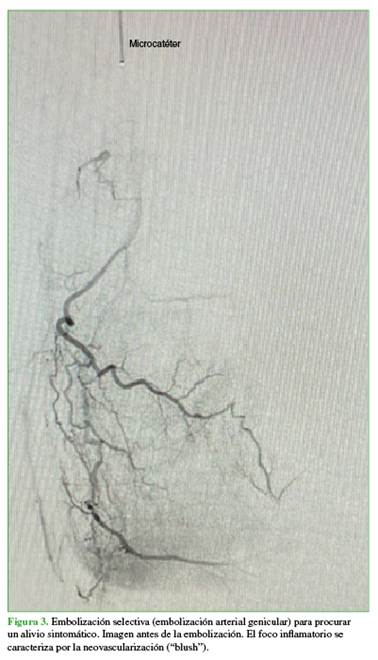

El paciente refiere franco alivio sintomático tras la embolización (Figura 3).

La técnica consiste en la embolización superselectiva de ramas arteriales geniculares que irrigan áreas de neoangiogénesis sinovial, buscando una reducción controlada —aunque no la oclusión completa— del flujo hacia los vasos patológicos, con el objetivo de disminuir la inflamación y el dolor, minimizando, a su vez, el riesgo de isquemia en tejidos vecinos (Figura 4).13